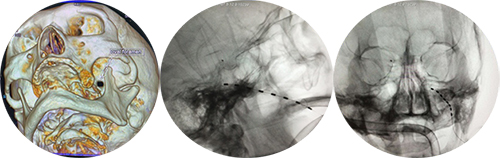

近日,山东第一医科大学附属省立医院(山东省立医院)疼痛科顺利完成省内首例三叉神经半月节神经电刺激置入术,为患者解除了痛苦。

孙涛教授及其医疗团队对滕大爷的病情进行了细致分析,并与滕大爷及其家属充分讨论,决定采用三叉神经半月节神经电刺激疗法。在排除手术禁忌后,疼痛科为其进行了微创手术,将电极成功放置在了三叉神经半月节的位置。

随着刺激器的开启,滕大爷左侧面部感觉到持续的酥麻感,原来频繁发作的疼痛神奇地缓解了一大部分。经过一周的调控,滕大爷的疼痛基本消失,终于摆脱了病痛的折磨。